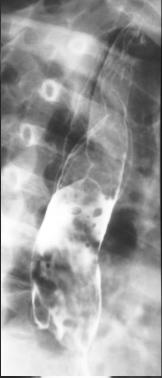

Image TOGD en double de contrast : Tumeur

intramurale bord lisse reduisent l /2 lumiere

de oesophage |

Leiomyome 1/3 inferieure de oesophge

: L lumiere de oesophge est redusent par une

refoulement reguliere de l muqueuse |